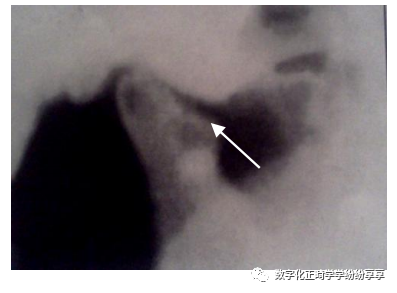

髁突小凹陷缺损

曲面断层片怎么看正畸【曲面断层片(全景片)】如何解读和查看:牙周?牙体?牙髓?关节?_https://www.jmylbn.com_新闻资讯_第29张

髁突经咽侧位片示髁突前斜面骨质呈小的凹陷状缺损,周围骨质密度减低

髁突前斜面广泛破坏

曲面断层片怎么看正畸【曲面断层片(全景片)】如何解读和查看:牙周?牙体?牙髓?关节?_https://www.jmylbn.com_新闻资讯_第30张

髁突经咽侧位片示髁突前斜面密质骨边缘消失,表面不整齐,有较广泛的骨质侵蚀及破坏